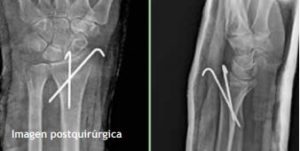

Caso 1.- Masculino de 52 años de edad con fractura de radio distal y estiloides cubital, se realizó reducción incruenta y fijación percutánea con 2 clavos de Kirschner obteniéndose una adecuada reducción y estabilidad. (fig. 2)